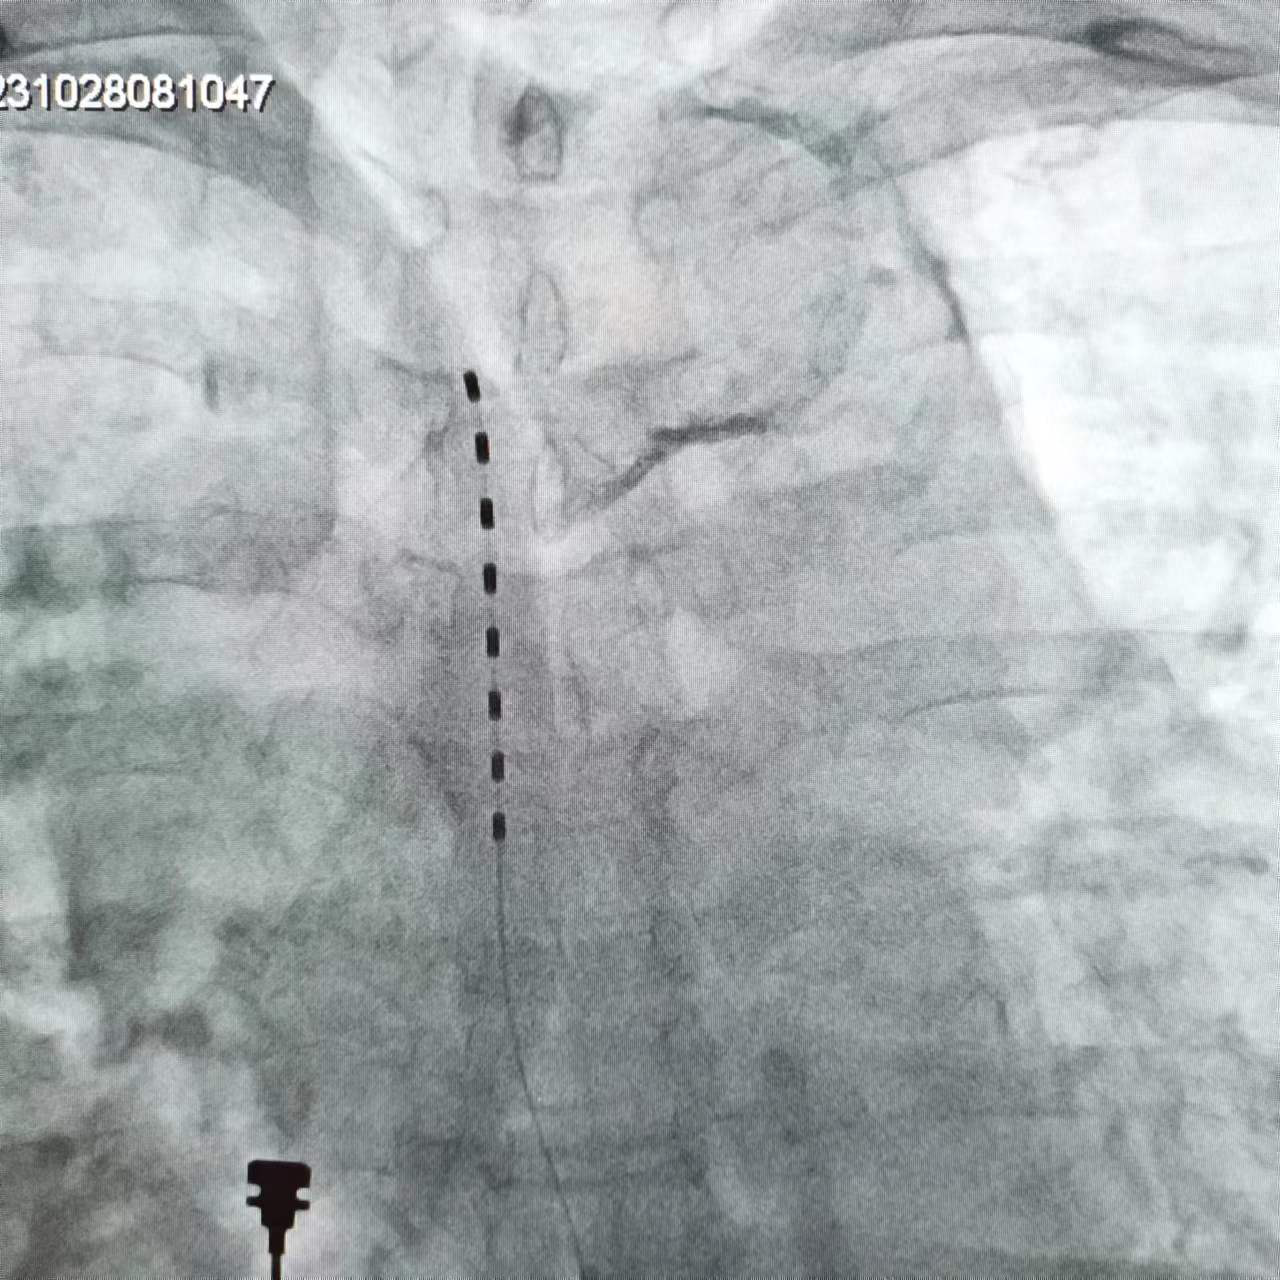

微创介入是控制疼痛的关键手段,急性期和后遗症期均适用,可以有效控制疼痛,也是目前疼痛科常用的技术手段。

神经阻滞:急性期应尽早开展,通过在神经周围注射消炎镇痛药、局麻药、营养神经药物等,可有效降低神经敏感性、控制炎症水肿,阻断疼痛传导,能有效降低后遗痛发生率。

神经调控:包括神经射频、电刺激等,是目前治疗带状疱疹后神经痛最有利的手段。通过干预神经电信号,减少疼痛传递,促进镇痛物质释放,可以达到更佳持久的镇痛效果。尤其适用于后遗神经痛的治疗。